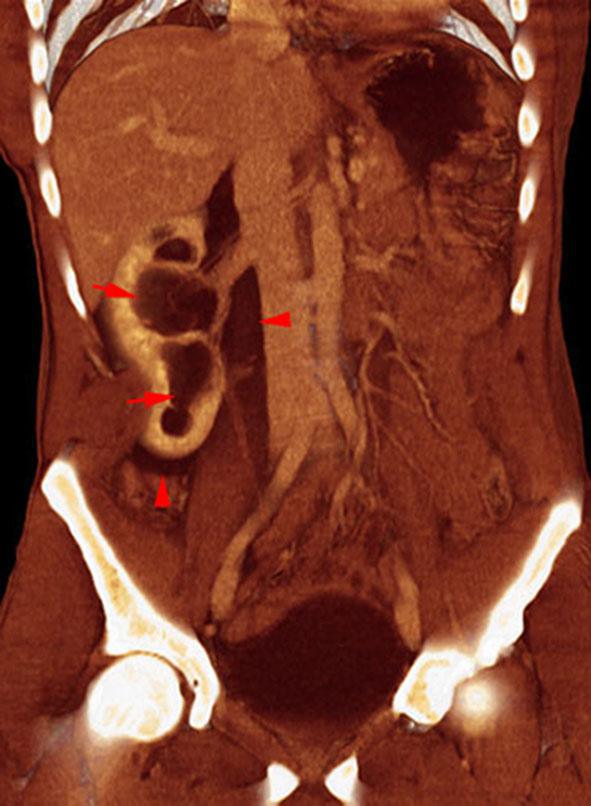

Rotura pielocalicial

VR seccional. Visión coronal anterior. TC contrastado en fase venosa. Nefromegalia derecha. Hidronefrosis (flechas) con presencia de líquido en los espacios pararrenal anterior y perirrenal (puntas de flecha). Integridad de uréter y pedículo vascular